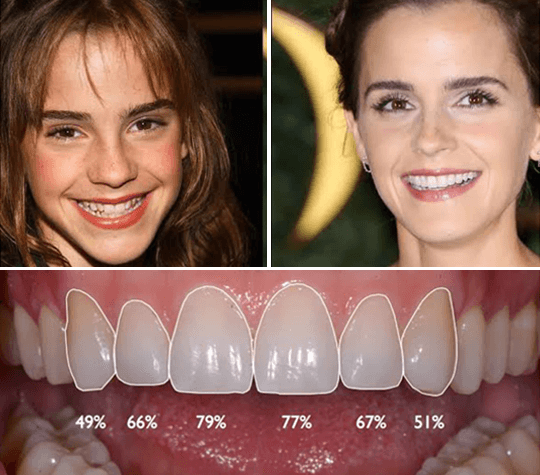

Real Patient Transformations

See the life-changing results achieved by our international patients.

Before

Before After

AfterDental Implant Smile Makeover